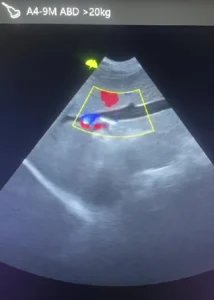

Ecografía Veterinaria para Perros y Gatos en Medellín (Envigado)

Ofrecemos servicio de ecografía veterinaria con equipos ecográficos modernos y personal capacitado para brindarte resultados confiables en poco tiempo.